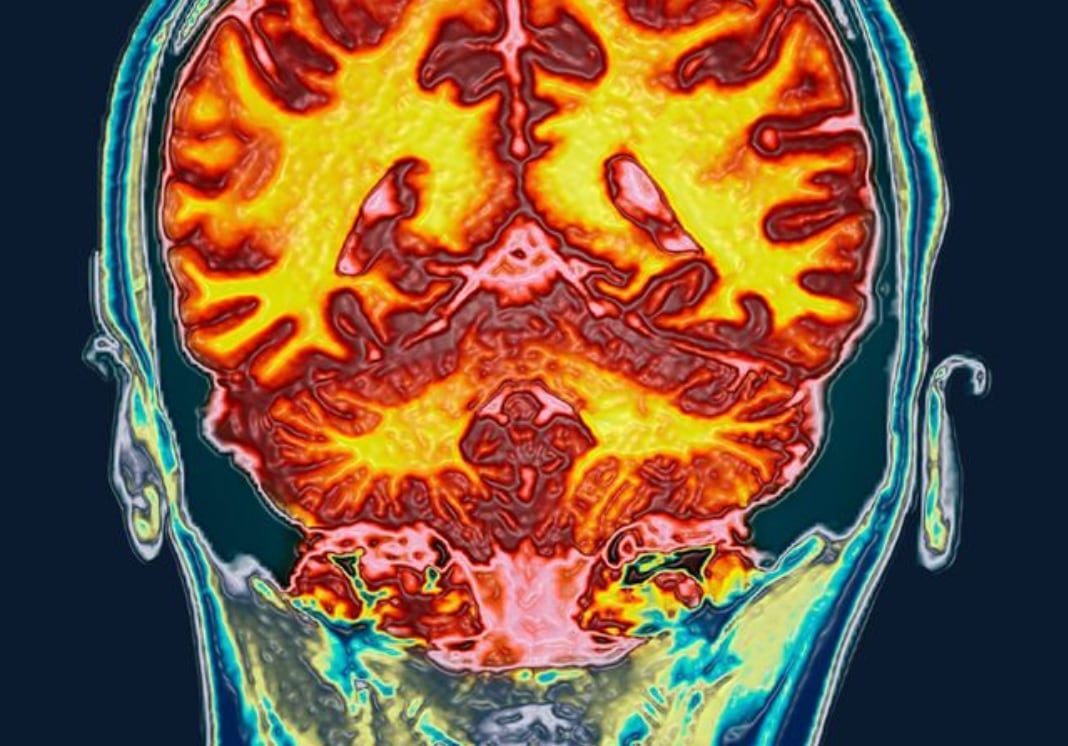

Aunque desde el año pasado un grupo de investigadores de la Universidad de California estudian la manera en la que el cerebro se ve afectado durante el ciclo menstrual, una nueva imagen muestran cómo el grosor de ciertas regiones se expanden durante el periodo.

Las fotografía, compartida por la revista National Geographic, evidencia el impacto sobre el cerebro, no solo desde su morfología, además su arquitectura funcional.

National Geographic adelantó que, las recientes resonancias magnéticas de cerebro femeninos recibidas por esto, muestran que la subida y bajada de las hormonas sexuales durante el ciclo menstrual modifica drásticamente la estructura del cerebro.